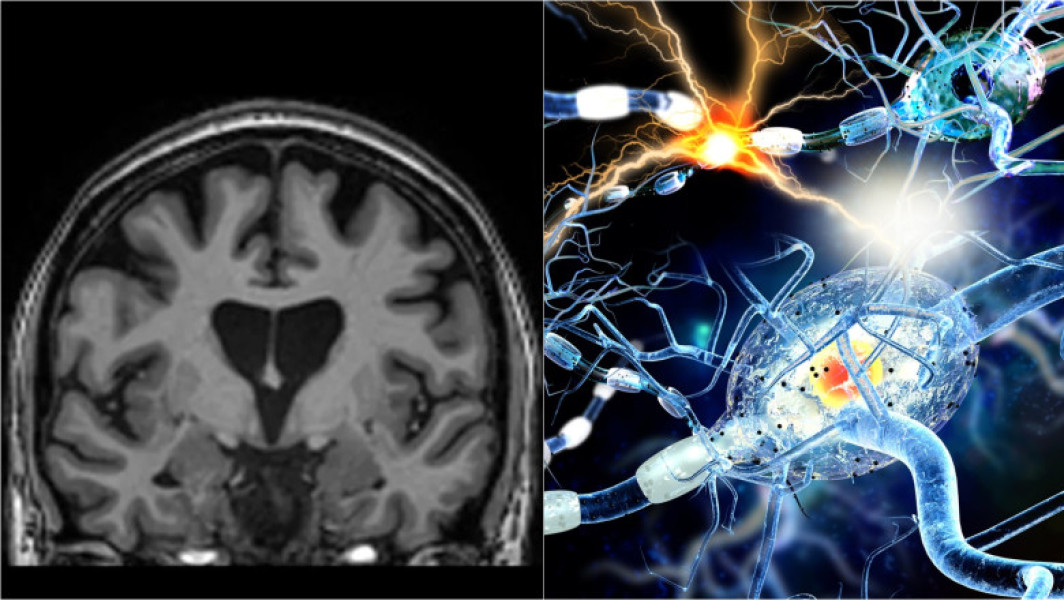

O premieră în tratarea bolii Huntington a fost realizată de compania de biotehnologie UniQure din Amsterdam. Studiul lor a arătat o reducere cu 75% a progresiei bolii la pacienții care au primit un tratament genetic inovator, ce utilizează o tehnică bazată pe micro-ARN. Această boală produce simptome grave, precum spasme involuntare, pierderi de memorie și modificări de personalitate, fiind fatală în cele din urmă.

Boala Huntington rezultă dintr-o mutație genetică în care tripletele C, A și G sunt repetate excesiv în ADN-ul ce codifică proteina huntingtin. Spre deosebire de alte boli ereditare, este suficient ca o singură genă defectă să fie moștenită de la unul dintre părinți pentru ca persoana să fie afectată. Această proteină anormală se acumulează și distruge neuronii, iar simptomele apar de regulă după vârsta de 30 de ani, boala fiind fatală în aproximativ 20 de ani.

Potrivit digi24.ro, tratamentul include implantarea în creier a unui virus modificat genetic care livrează o secvență de ADN specială ce transformă neuronii în fabrici ce produc molecula micro-ARN AMT-130. Această moleculă blochează producția proteinei toxice. Studiul a inclus 29 de participanți din America și Europa și a durat trei ani, arătând o încetinire semnificativă a evoluției bolii, cu puține efecte secundare.